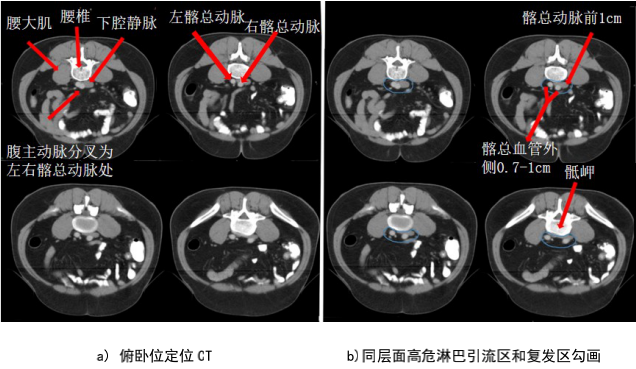

CTV 上界主要涉及盆腔骶前區(PS)以及髂內淋巴引流區(LLN P)上界,PS 上界建議采用骶岬;LLN P 上界在不遺漏轉移淋巴結的前提下,建議選擇骶岬,以減少對腸道的照射。對于高位直腸癌術前放療,直腸系膜區(M)下界建議包括至腫瘤下緣下 3~5 cm 即可,不必要包全所有的直腸系膜(有淋巴結轉移情況除外);直腸中、下段癌做術前放療,常規包全直腸系膜區。臨床上對側方淋巴結(LLN P,LLN A)是否轉移,其診斷準確性不高;確認有側方淋巴結轉移情況應根據具體醫療中心的多學科診療意見進行處理。是否預防性照射腹股溝淋巴引流區(IN),專家意見不統一,通常的經驗是,對于腫瘤負荷大、區域淋巴結轉移多的患者,同時存在侵犯肛門周圍皮膚或下 1/3 陰道情況,推薦預防照射 IN;而對于 T 分期偏早的腫瘤,特別是同時存在 N0 情況,即使腫瘤侵犯肛門周圍皮膚或下 1/3 陰道,也可以考慮不預防照射 IN。對于坐骨直腸窩(IRF)未受累的情況,術前放療需謹慎照射 IRF,以減少手術并發癥;即使腫瘤侵犯 IRF,僅需要照射受侵部分,不需照射整個IRF。

CTV 及 CTVp 外擴至 PTV 的數據需根據各單位自己的經驗,或者參考 RTOG 的建議,三維在腹背方向外擴 0.7~1.0 cm、頭腳方向外擴 1 cm,不包括皮膚(2B 級證據)。

腹部骶前區-PS S (青色) (圖 5),邊界:

上界:腹主動脈分叉為左、右髂總動脈處或該區域內轉移淋巴結上方至少 0.5 cm;

下界:骶岬;

前界:腰椎前方 1 cm,髂總血管前 1.0 cm;

后界:腰椎前緣;

外界:髂總血管外側外 0.7~1.0 cm。

盆腔骶前區-PS (淡藍色) (圖 6),邊界:

上界:髂總動脈分叉為髂內、外動脈處/骶岬;

下界:肛提肌插入外括約肌處/直腸周圍系膜脂肪組織消失處,相當于尾骨尖水平;

前界:腰椎前方 1.0 cm/骶骨尾骨前方 1 cm/直腸系膜筋膜后緣;

后界:腰椎前緣/骶骨尾骨前緣;

外界:骶髂關節/髂肌內緣。

i) 高危復發區合集圖(CT 層厚 0.5 cm,俯臥位)(圖 14)。下表 示出高危復發區顏色。

表 直腸癌高危復發區顏色

圖 14 直腸癌高危復發區合集圖